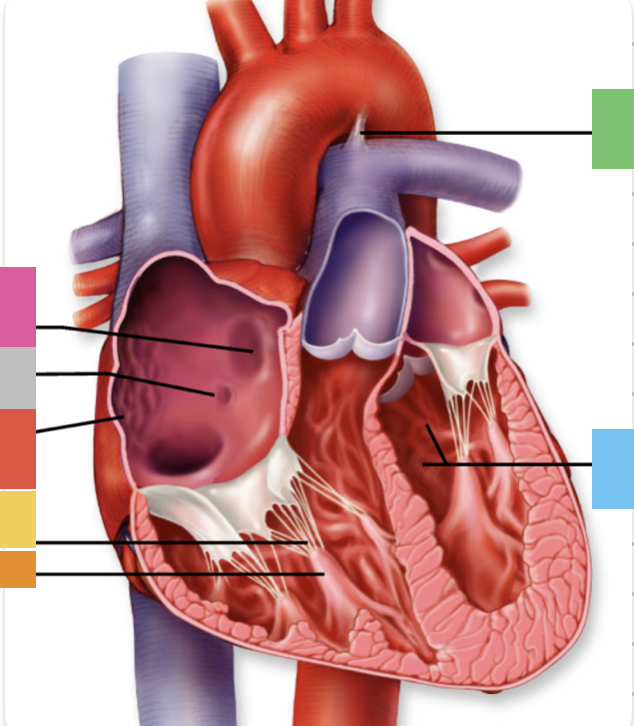

light purple

base

purple

apex

grey

right atrium

pink

right auricle

green

left atrium

green

left auricle

blue

right ventricle

orange

left ventricle

green

coronary (atrioventricular) sulcus

pink

interatrial septum

dark blue

interventricular septum

green

anterior interventricular sulcus

green

posterior interventricular sulcus

orange

aortic valve

yellow

pulmonary valve

red

tricuspid valve (right AV)

purple

bicuspid valve (left AV)

yellow

chordae tendineae

orange

papillary m.

blue

trabeculae carneae - only in ventricles

red

pectinate m. - only in R atrium

pink

fossa ovalis

grey

opening of coronary sinus